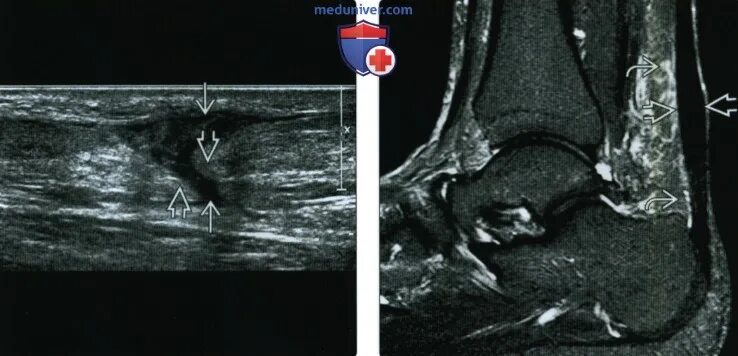

Мрт ахиллового сухожилия